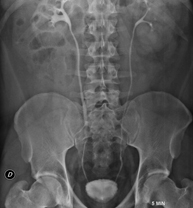

- IVU (Retrograde pyelography)

Intravenous urography (IVU) involves serial radiological imaging of the kidney, urinary tract and bladder. This study always requires the use of an iodinated contrast agent.